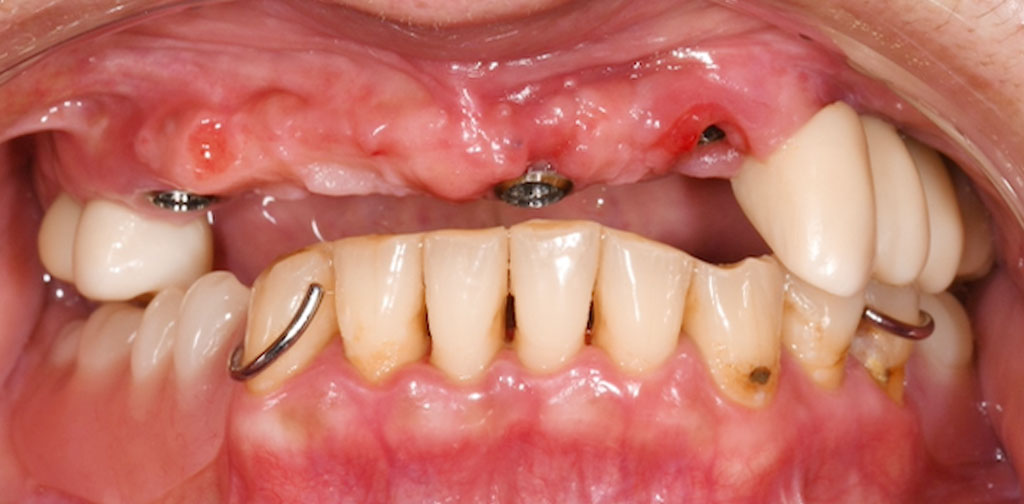

Before1

50代女性・横浜市在住。長らく入れ歯生活を強いられていたが、不便さを感じ、インプラント治療を希望されてご来院されました。

術前検査(歯周病菌の検査(PCR検査)を行ったところ、Pg菌、Td菌、Tf菌の数値は問題なし。

左上1,2番、右上4番はぐらつきがあるため、抜歯。通常手術にて、左上1,2番、右上4番の骨にインプラントを埋め込みました。